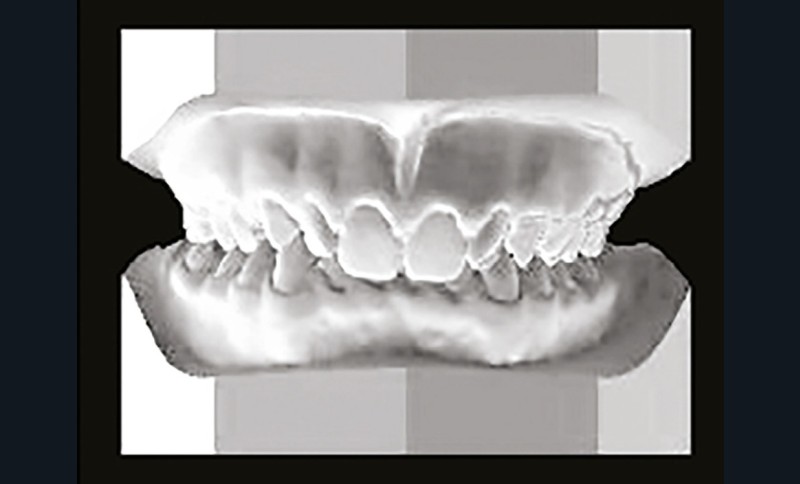

Son profil convexe s’inscrit dans un contexte de classe II squelettique par rétrognathie mandibulaire normodivergente sur un schéma de Classe II/2 avec supraclusion et encombrement modéré (fig. 1 à 7).

La formule dentaire est complète, avec un léger retard d’évolution des deuxièmes molaires (fig. 8).